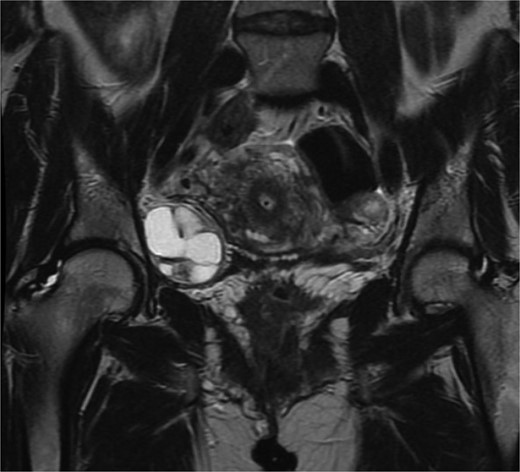

A 40-year-old P4 woman, with a past medical history of celiac disease, hypothyroidism, and varicose veins, presented with intermittent right lower quadrant pain that occurs 1–2 times per week for over a year, exacerbated by sexual activity. She denied any changes in urinary habits, bowel movements, or early satiety. Transvaginal ultrasound measured the right ovary at 4.5 × 4.3 × 3.8 cm with a complex cyst measuring 4.6 × 3.3 × 3.6 cm and containing several cystic spaces with low-level internal echoes. Prior imaging showed the cyst had been slowly growing with dimensions from one year ago (Fig. 1) at 4.2 × 3.7 × 3.6 cm and three years ago at 2.8 × 2.1 × 1.6 cm. Magnetic resonance imaging (MRI) of the pelvis (Fig. 2) revealed a complex solid and cystic retroperitoneal mass abutting the right external iliac vessel. Although the patient reported only intermittent pain at this time, the continued increase in size was concerning for a potential neoplasm. Although malignancy could not be ruled out, the absence of elevated tumor markers like CA-125 suggested a benign finding. The decision was made to proceed with diagnostic laparoscopy for suspicion of growing ovarian lesion. The diagnostic laparoscopy successfully visualized normal-appearing ovaries and fallopian tubes bilaterally. However, a 4-cm firm, circumferential retroperitoneal mass within the right broad ligament along the sidewall of the pelvis was discovered. Due to the mass’s location and proximity to the right ureter and uterine artery, dissection was not attempted in favor of conservative treatment and monitoring.

Coronal magnetic resonance imaging of the pelvis with contrast. Complex solid and cystic retroperitoneal mass abutting the right external iliac vessel, 4.4 cm × 4.0 cm × 3.8 cm in measurement.